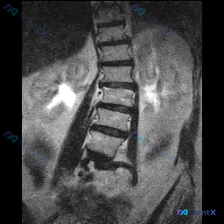

整理到一份腰椎MRI的影像分析资料,第一眼看到的是很明确的脊柱问题: - 腰椎向右侧凸,凹侧在左 - 多节段椎间盘T2信号减低,凹侧椎间隙更窄 - 椎体边缘有骨赘形成 但再往下看,影像里还提到了一个脊柱外的意外发现,而且风险等级可能比脊柱侧凸更高… 想先问问大家:如果是你拿到这份只有冠状位的腰椎MR...